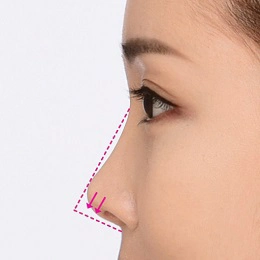

بینی رو به بالا یا بینی کوتاه به بینی ای اطلاق می شود که نسبت به صورت شخص بسیار کوتاه است. و در نمای جلویی دارای سوراخ های بینی بیش از حد قابل مشاهده است. بینی کوتاه یکی از بزرگترین چالش های جراحی زیبایی بینی است. این نوع بدشکلی معمولاً هر 3 لایه بافت بینی (یعنی پوست، پوشش داخلی، حمایت از استخوان) را درگیر می کند. بینی های کوتاه هم مشکلات زیبایی و هم نقص عملکردی دارند. زمانی که رینوپلاستی بینی کوتاه به طور ماهرانه انجام شود، می تواند بهبود چشمگیری ایجاد کند.

بینی کوتاه کلاسیک به سمت بالا و حالت فرورفتگی دارد به طور خاص، به عنوان بینی بدون ابعاد از زاویه نازو فرونتال تا نوک تعریف می شود. فقدان برآمدگی نوک اغلب در تشخیص وجود دارد. برای تعیین اینکه آیا بینی کوتاه وجود دارد، جراح ابتدا باید از ابعاد بینی طبیعی آگاه باشد. هنگام شناسایی بینی کوتاه، تجزیه و تحلیل تمام صورت، به ویژه نیمرخ، همراه با آنالیز به ویژه بینی انجام می شود.

حالت بینی زاویه دار رو به بالا

پوست و بافت های نرم نوک بینی با زاویه رو به بالا برداشته می شوند، سپس نوک بینی بعد از اینکه به سمت پایین کشیده شود ثابت می شود و غضروف اصلاح می شود تا بلند به نظر برسد.